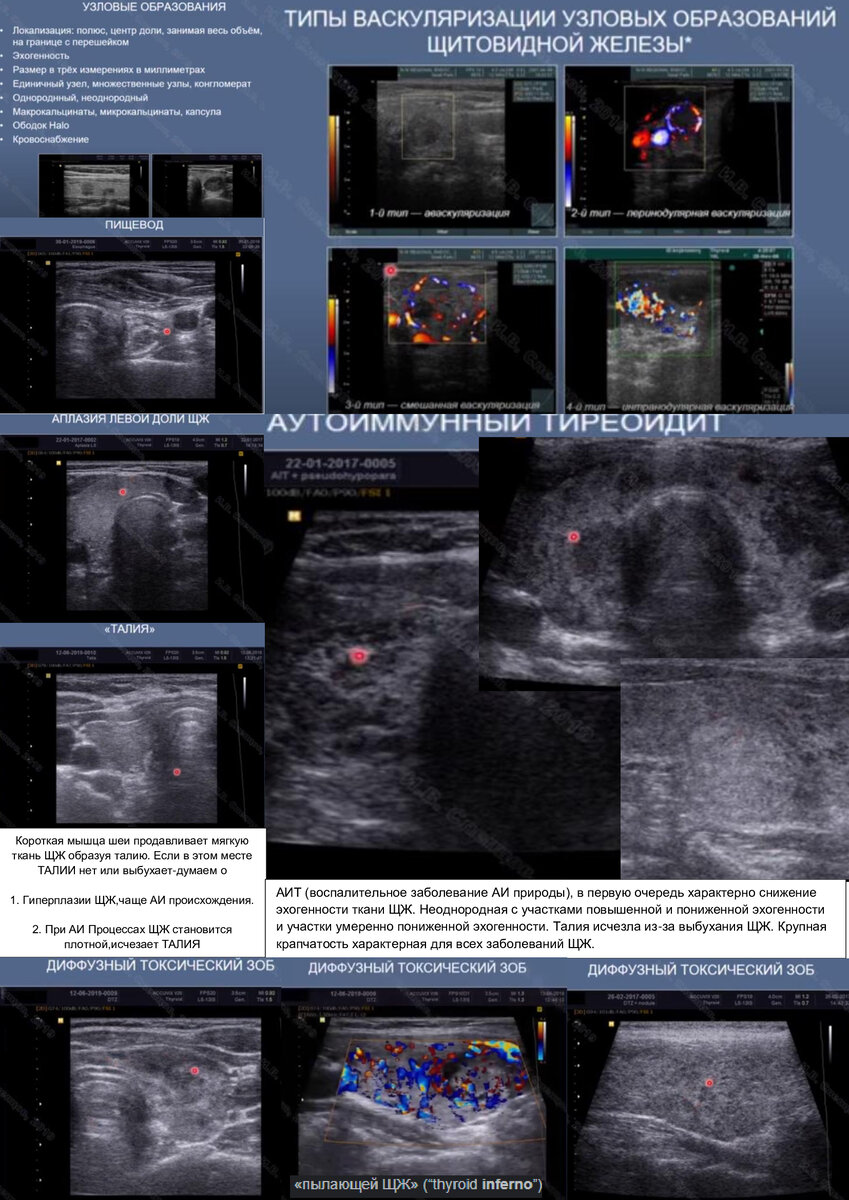

В структуре патологии ЩЖ преобладает носительство (АТ-ТПО) в сочетании с УЗ признаками АИТ (диффузная неоднородность и снижение эхогенности ткани ЩЖ), отмеченное в группе бесплодных женщин в 2,8 раза чаще, чем у фертильных.

Как известно, АИТ является основной причиной спонтанного гипотиреоза. Если диагностика гипотиреоза не вызывает особых сложностей (определение уровня ТТГ), то при отсутствии снижения функции ЩЖ диагноз АИТ зачастую носит лишь вероятностный характер. Диагноз АИТ может быть установлен только при наличии «больших» диагностических признаков: первичного гипотиреоза (манифестного или стойкого субклинического), наличии антител к ткани ЩЖ и ультразвуковых признаков аутоиммунной патологии. При отсутствии хотя бы одного из «больших» диагностических признаков диагноз АИТ носит лишь предположительный характер.